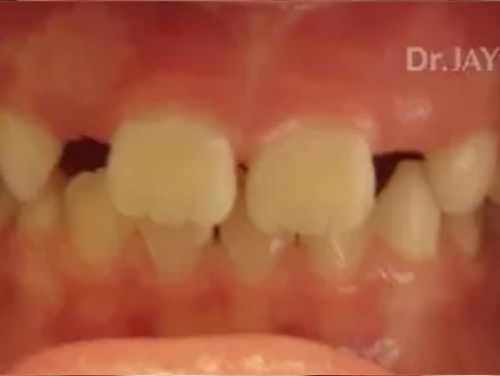

Severe crowding , parent had gone for a consult with 4 Orthodontist to resolve crowding. Orthodontist recommended extraction of multiple teeth to resolve crowding and straighten teeth. At Dr.Jay Dental , Dr. Jay finished the case with no extractions of teeth and just expansion of upper and lower jaws to accommodate all teeth.

Before

After